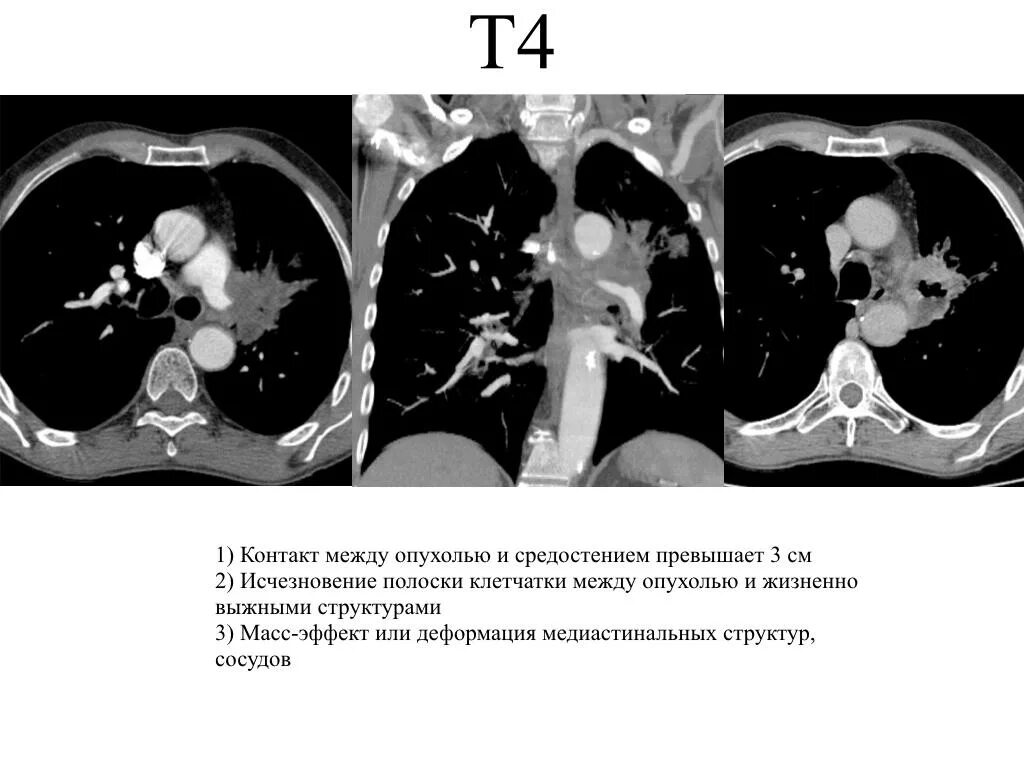

Метастазы 4 степени в легких